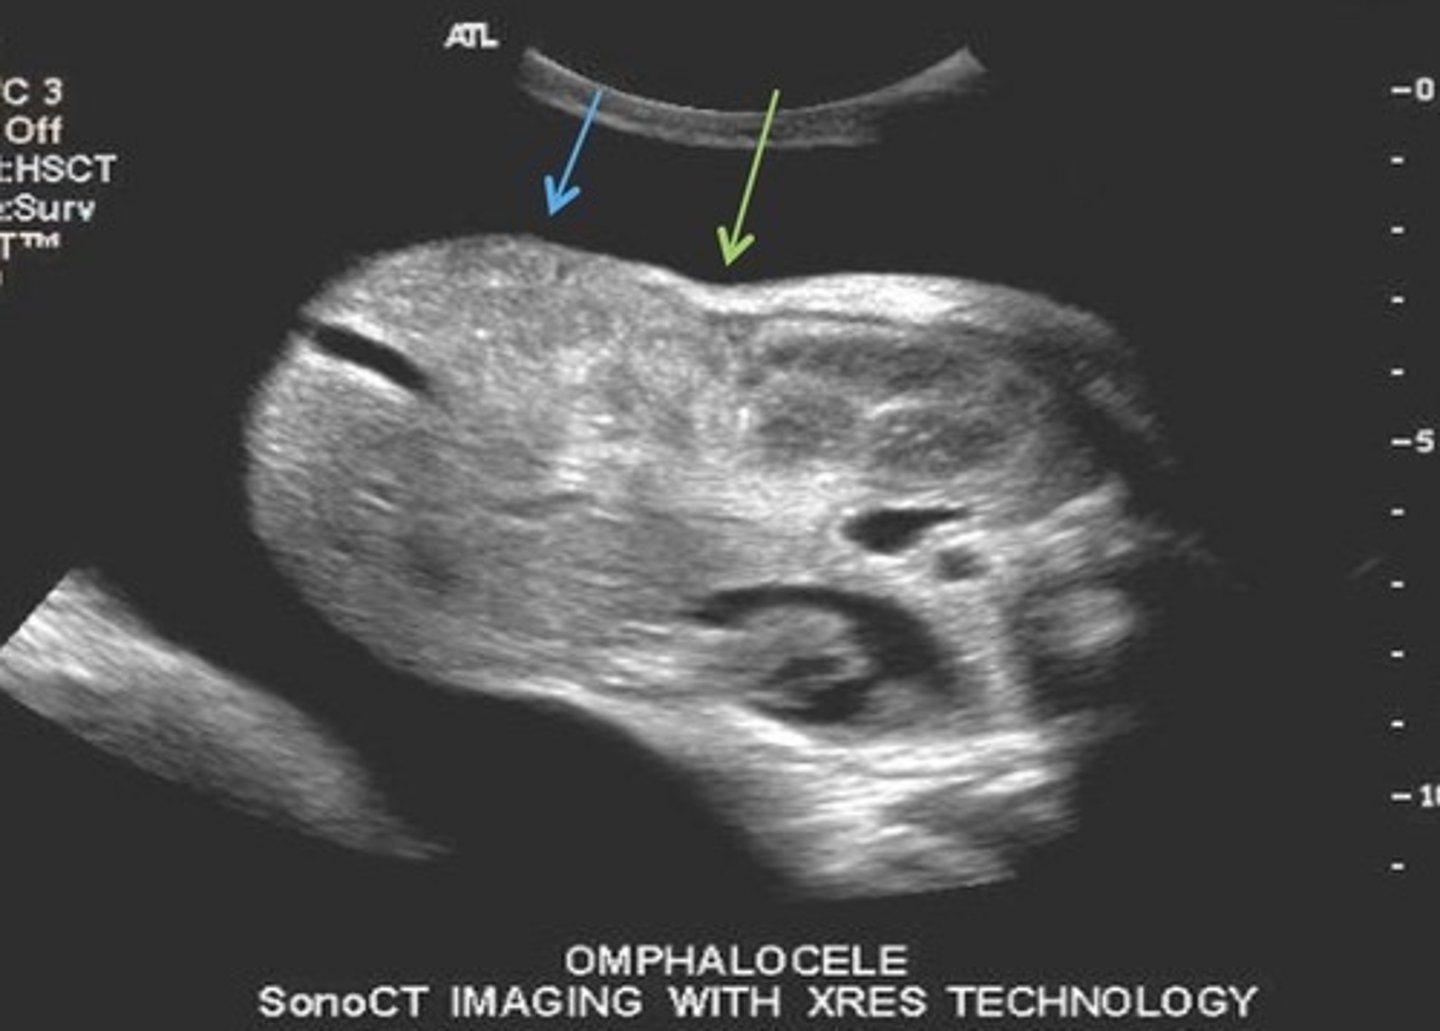

Omphalocele

Herniation of bowel into umbilical cord after 13 weeks

Type 1 Omphalocele

Contains only bowel

80% association with aneuploidy's

Type 2 Omphalocele

Contains bowel and liver

20% association with aneuploidy's